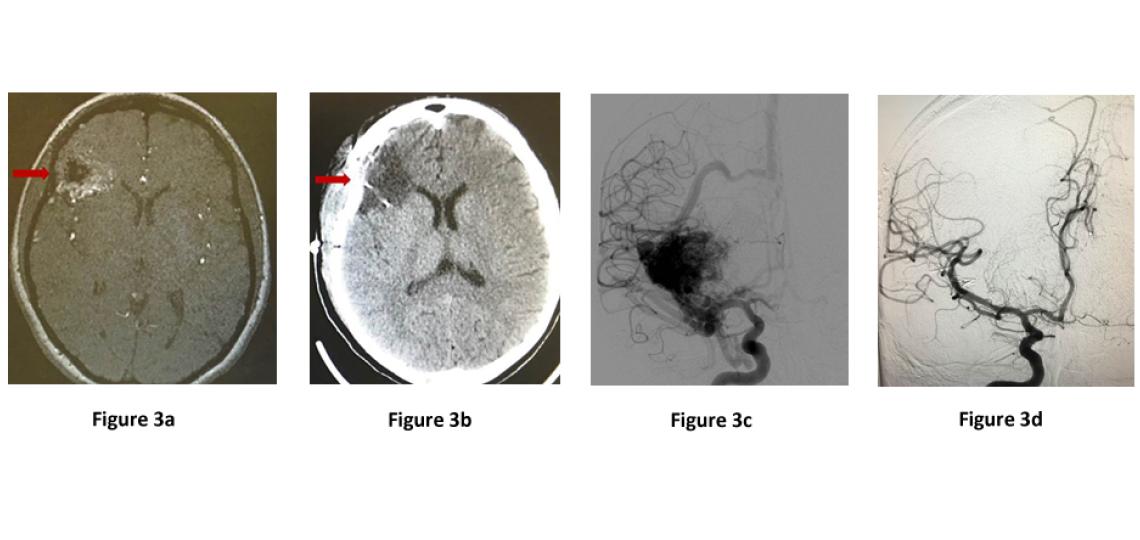

The goal of AVM treatment is to prevent bleeding from the AVM. When an AVM bleeds, it can damage the surrounding brain tissue with mild to serious consequences (Figure 2). Some of the problems encountered after AVM rupture can include body weakness, loss of speech, numbness, paralysis, coma and even death.

Figure 2a: Brain CT scan showing bleeding (arrow) in the brain. Figure 2b: CT angiogram showing bleeding in the brain (blue arrow) and nearby AVM vessels (red arrow) that caused the bleed. Figure 2c: Brain angiogram showing the abnormal vessel tangle (arrow).